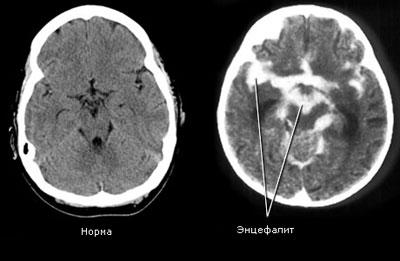

- Энцефалит и менингит. Оба заболевания имеют инфекционную этиологию и имеют ярко выраженные симптомы интоксикации. В обоих случаях показано стационарное лечение.